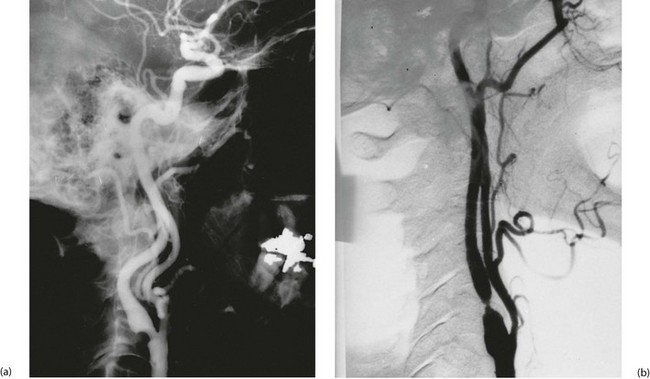

• Acute thrombotic or embolic obstruction (Fig. 42.8). This is analogous to acute thrombosis or embolism of the lower limb described in Chapter 41. The cause is usually superior mesenteric artery occlusion and the condition presents as an ‘acute abdomen’ (see Ch. 19)

The rare condition of chronic mesenteric ischaemia or ‘gut claudication’ occurs when the visceral blood supply is restricted to a point where it becomes inadequate during active digestion but remains adequate at rest. This occurs when there is gross atherosclerotic narrowing of all three main mesenteric vessels (coeliac, superior mesenteric and inferior mesenteric arteries). These patients present with severe epigastric pain on eating which causes ‘fear of food’. There is always gross weight loss and sometimes an epigastric bruit can be heard on auscultation.

Diagnosis is by arteriography with lateral views showing the origins of the three main vessels or CT angiography. Treatment is by stenting or surgical reconstruction of the origins of one or more mesenteric arteries.